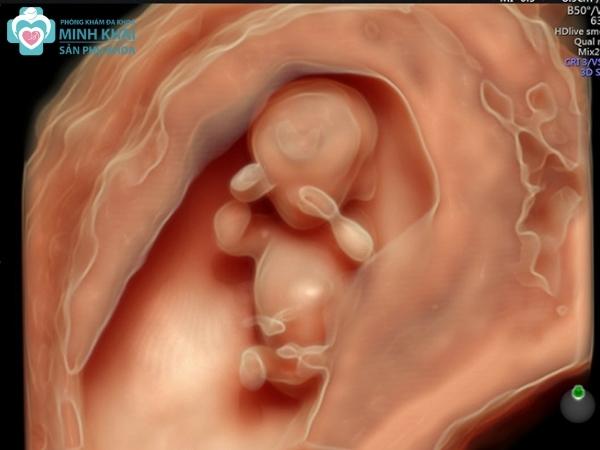

Siêu âm thai 5D

Siêu âm thai 5D là phương pháp siêu âm hiện đại nhất hiện nay. Nó phát triển từ công nghệ siêu âm 4D và tích hợp thêm một chiều chức năng là chiều chẩn đoán tự động. Theo đó hệ thống sẽ tự động tái tạo, tính toán và phân tích hình ảnh thai nhi theo khung chuẩn đề bác sĩ có thể dễ dàng đánh giá cũng như phát hiện ra những bất thường.

Hình ảnh siêu âm 5D thể hiện rõ ràng tổng quan cấu trúc cơ thể bên ngoài cũng như hệ tim mạch, nội tạng, hệ tuần hoàn máu bên trong thai nhi. Qua siêu âm 5D, 1 chu chuyển tim cùng với 9 mặt cắt cơ bản, thông số thường quy để khảo sát tim được trình bày rất đầy đủ. Bên cạnh đó, siêu âm 5D còn thể hiện được toàn bộ hệ thần kinh trung ương qua 3 mặt cắt não cơ bản để giúp bác sĩ đưa ra những chẩn đoán chuẩn xác nhất.

Siêu âm 5D chính là sự phát triển về công nghệ của siêu âm 4D khi được kết hợp thêm 1 chiều chẩn đoán tự động.